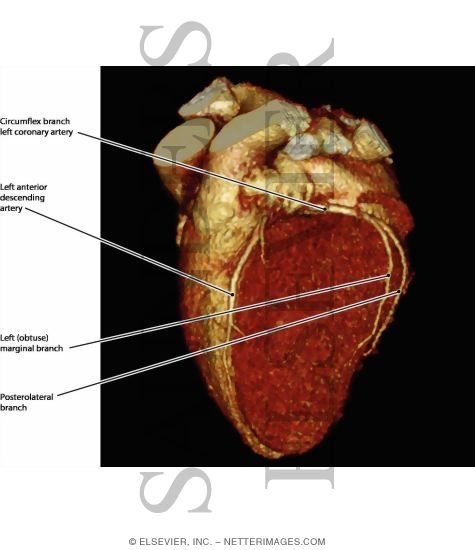

Coronary Vessels, Anterior View

Coronary Vessels: Anterior View